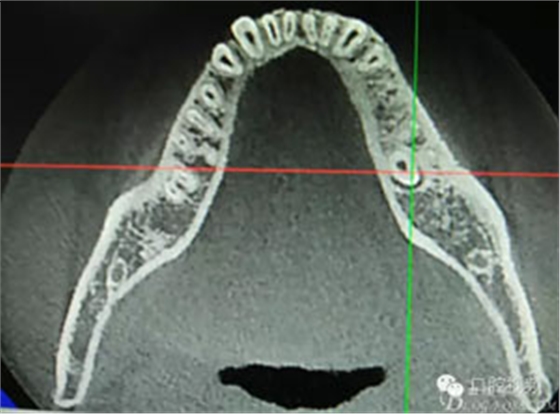

圖3.術(shù)前口內(nèi)照片,舌側(cè)外形無隆起。光滑平整。